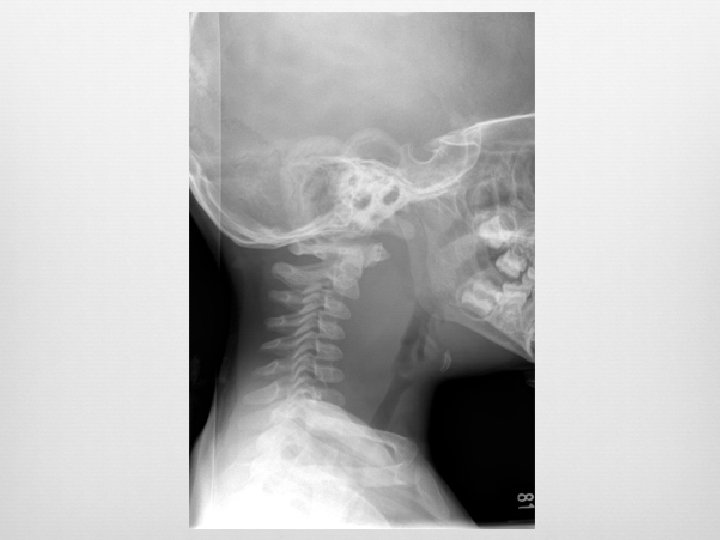

Epiglottitis Enlarged epiglottis Loss of valecular airspace Thickened aryepiglotic folds Distended hypopharynx Straightening of the cervical spine Sensitivity (38 -88%) Specificity (78%) Croup and epiglottitis: a radiologic study. AU Stankiewicz JA; Bowes AK SO Laryngoscope 1985 Oct; 95(10): 1159 -60. Epiglottitis and croup. AU Sobol SE; Zapata S SO Otolaryngol Clin North Am. 2008 Jun; 41(3): 551 -66, ix. Adult epiglottitis: the Toronto Hospital experience. AU Solomon P; Weisbrod M; Irish JC; Gullane PJ SO J Otolaryngol. 1998 Dec; 27(6): 332 -6.

Case 1 4 year old male Inspiratory stridor Unwell for past 24 hours Mom found him in his room with increased work of breathing